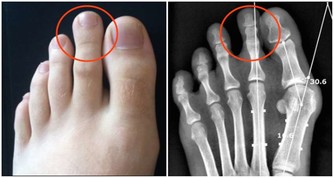

我的喉嚨偶爾會跑出米粒大小,黃白色的不明顆粒,

不會痛也不會不舒服,

但就是很臭,

這個症狀少說也有十幾年了,

我原本以為那是沒消化完的飯粒之類的,

後來我把關鍵字丟到谷歌,

才發現原來這是扁桃腺結石,

很有可能就是我口臭的主因,

另 外,蔡立泰醫師也表示,扁桃腺結石通常看起來像白色或微黃色的小石頭,有時候吐出來時,可以把這些小石頭壓碎,並出現臭臭的味道。扁桃腺結石目前 大多認為是由食物的殘渣及壞菌卡在扁桃腺表面的隱窩中所形成。有些人會感覺到喉嚨卡卡的感覺,嚴重的患者更可能出現頭痛、咽喉疼痛、吞嚥困難、耳朵痛癢、 甚至嘔吐等情形。也因為這些細菌和食物的殘渣以及部分壞死組織的鈣化,所以可能在講話時散發出一些腐爛的臭味,也就是我們所謂的口臭。